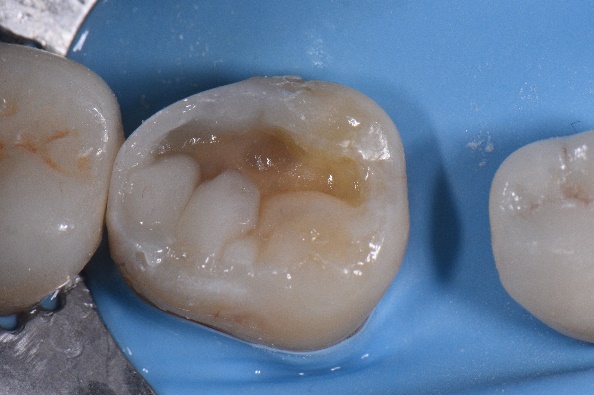

Fig. 2 Îndepărtarea restaurării preexistente la nivelul 4.7.

Fig. 3 Aplicarea de straturi subţiri de compozit la nivelul proximal al cavităţii